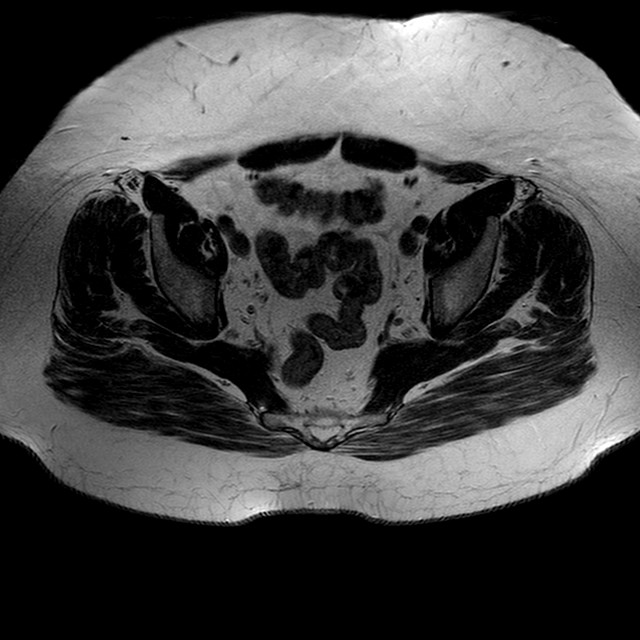

Esami: RMN BACINO

T2w TSE

Evidenti e simmetriche alterazioni osteofitosiche in regione coxo femorale con riduzione delle rime articolari. Degenerazione completa del cercine glenoideo. Non attuali segni di versamento articolare. Non segni di edema osseo che escludono attuale algodistrofia od osteonecrosi. Lieve e simmetrica riduzione del trofismo della muscolatura glutea.